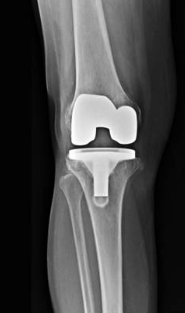

Prothèse totale de genou

Cette prothèse est destiné aux arthroses évoluées du genou